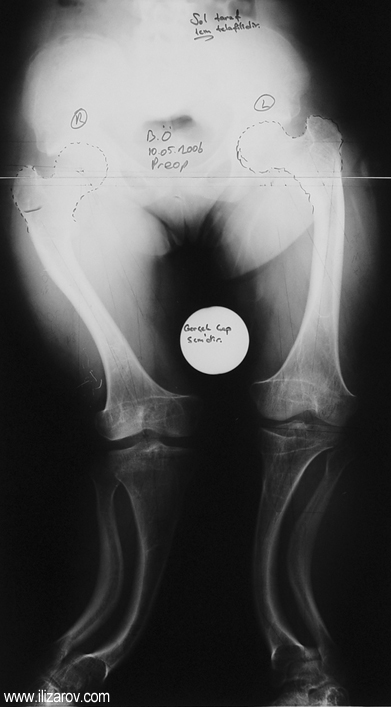

In hypophosohatemic rickets, abnormal bone findings become evident after 1 year of age; there are short stature and deformities around the knee (bilateral genu valgum or varum, tibial torsion, deformity at tibia and femur, ‘windswept’ deformity).

Before surgery, laboratory values are checked and the appropriate treatment is applied by the endocrinology department. The patients can be operated after they receive calcitriol (vitamin D) and phosphate treatment for at least 6 months and laboratory values return to normal. Endocrinologic follow-up continues after surgery.

Because the deformity caused by hypophosphatemic rickets is very close to the growth plate, a significant deformity and malalignment occurs. For that reason, more than one deformity centers (CORA) are found at preoperative evaluation, and osteotomy at more than one level is required to correct the deformity. The most frequently used methods to correct the deformity are acute or gradual deformity correction using the Ilizarov method or unilateral external fixator. In the ‘fixator assisted nailing’ technique, which is applied in our department, the deformity is corrected in an acute fashion with the help of an external fixator, and the extremity is stabilized by an intramedullaru nail. The external fixator is removed before the end of the surgery if no gradual lengthening is planned postoperatively. If lengthening (over nail) is planned, the fixator is removed after the completion of the lengthening procedure. As a result, the risk of pin tract infection is eliminated, correction loss and relapsing of the deformity (which are important problems in the treatment of hypophosphatemic rickets) are avoided, eary motion and full weight bearing are allowed, and comfortability of the patient is improved because the duration with external fixator is decreased.